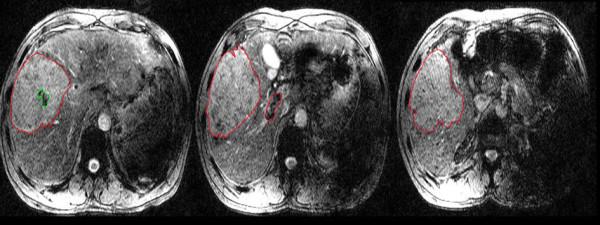

Neoplastic and bland portal vein thrombi (PVT) are both common in patients with hepatocellular carcinoma (HCC). The correct discrimination of them is essential for therapeutic strategies planning and survival predicting. The current study aims to investigate the value of susceptibility-weighted imaging (SWI) in differentiating bland from neoplastic PVT in HCC patients.

20 HCC patients with bland PVT and 22 HCC patients with neoplastic PVT were imaged with non-contrast SWI at 3.0 Tesla MRI. The signal intensity (SI) of the PVT and HCC lesions in the same patients was compared on SW images. The phase values of the PVT were compared between neoplastic and bland thrombi cohorts. Receiver operator characteristics (ROC) analysis was conducted to evaluate the diagnostic ability of the phase values for neoplastic and bland thrombi discrimination.

20 of 22 neoplastic PVT were judged similar SI and 2 were judged lower SI than their HCC. For 20 bland PVT, 19 were judged lower SI and 1 was judged similar SI as their HCC (P<0.001). The average phase values (0.361 ± 0.224) of the bland PVT were significantly higher than those of the neoplastic PVT (-0.328 ± 0.127, P<0.001). The AUC for phase values in differentiating bland from neoplastic PVT was 0.989. The best cut-off value was -0.195, which gave a sensitivity of 95% and a specificity of 95.5%.

SW imaging appears to be a promising new method for distinguishing neoplastic from bland PVT. The high sensitivity and specificity suggest its high value in clinical practice.